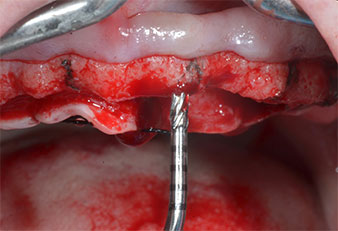

Uno strumento piezoelettrico (Piezomed I1) a forma di fiamma, rivestito in diamante, è stato usato per contrassegnare le posizioni dell'impianto e per eseguire una preparazione pilota (Fig. 3). Si è prestato attenzione a utilizzare un movimento verticale ascendente e discendente, con potenza ridotta, irrigazione completa e bassa pressione (inferiore a 300 g). Successivamente è stato applicato uno strumento pilota (Piezomed I2A/I2P) per l'ingrandimento iniziale delle sedi dell'impianto del diametro di 2 mm (Fig. 4), seguito da un inserto da 3 mm (Fig. 5).

Nel presente caso, gli strumenti Z25P e Z35P non sono stati utilizzati a causa dell'osso posteriore relativamente morbido, che è stato facilmente gestito mediante I3A/I3P.